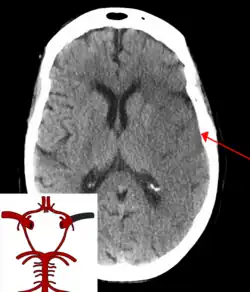

![]() | |

| CT scan of the brain showing a massive, prior right-sided ischemic stroke from blockage of an artery. Changes on a CT may not be visible early on.[1] | |

The most significant risk factor for stroke is high blood pressure.[7] Other risk factors include high blood cholesterol, tobacco smoking, obesity, diabetes mellitus, a previous TIA, end-stage kidney disease, and atrial fibrillation.[2][7][8] Ischemic stroke is typically caused by blockage of a blood vessel, though there are also less common causes.[13][14][15] Hemorrhagic stroke is caused by either bleeding directly into the brain or into the space between the brain's membranes.[13][16] Bleeding may occur due to a ruptured brain aneurysm.[13] Diagnosis is typically based on a physical exam and supported by medical imaging such as a CT scan or MRI scan.[9] A CT scan can rule out bleeding, but may not necessarily rule out ischemia, which early on typically does not show up on a CT scan.[10] Other tests such as an electrocardiogram (ECG) and blood tests are done to determine risk factors and possible causes.[9] Low blood sugar may cause similar symptoms.[9]

Diagnosis

Stroke is diagnosed through several techniques: a neurological examination (such as the NIHSS), CT scans (most often without contrast enhancements) or MRI scans, Doppler ultrasound, and arteriography. The diagnosis of stroke itself is clinical, with assistance from the imaging techniques. Imaging techniques also assist in determining the subtypes and cause of stroke. There is yet no commonly used blood test for the stroke diagnosis itself, though blood tests may be of help in finding out the likely cause of stroke.[76] In deceased people, an autopsy of stroke may help establishing the time between stroke onset and death.

Imaging

For diagnosing ischemic (blockage) stroke in the emergency setting:[77]

- CT scans (without contrast enhancements)

- sensitivity= 16% (less than 10% within first 3 hours of symptom onset)

- specificity= 96%

- MRI scan

- sensitivity= 83%

- specificity= 98%

For diagnosing hemorrhagic stroke in the emergency setting:

- sensitivity= 89%

- specificity= 100%

- sensitivity= 81%

For detecting chronic hemorrhages, an MRI scan is more sensitive.[78]

CT scans may not detect ischemic stroke, especially if it is small, of recent onset,[10] or in the brainstem or cerebellum areas (posterior circulation infarct). MRI is better at detecting a posterior circulation infarct with diffusion-weighted imaging.[79] A CT scan is used more to rule out certain stroke mimics and detect bleeding.[10] The presence of leptomeningeal collateral circulation in the brain is associated with better clinical outcomes after recanalization treatment.[80] Cerebrovascular reserve capacity is another factor that affects stroke outcome – it is the amount of increase in cerebral blood flow after a purposeful stimulation of blood flow by the physician, such as by giving inhaled carbon dioxide or intravenous acetazolamide. The increase in blood flow can be measured by PET scan or transcranial doppler sonography.[81] However, in people with obstruction of the internal carotid artery of one side, the presence of leptomeningeal collateral circulation is associated with reduced cerebral reserve capacity.[82]